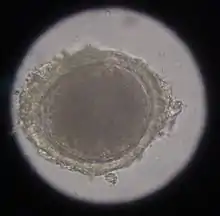

The most common roundworm in most cats is toxocara mystax (syn. toxocara cati), infestation with toxascaris leonina is less common. Only in ocelots in Texas was T. leonina detectable in every animal, making it the most common parasite,[2] and in bobcats in Nebraska it was observed almost as often as T. mystax.[3] Both species of roundworm occur worldwide and roundworm infestation is a very common endoparasitosis. The adult roundworms, up to 10 cm long, live in the small intestine. The female worms produce a large number of eggs, which are released into the environment with the feces. The infective larvae develop in the eggs after about four weeks.

In the case of worms in vomit, the diagnosis can already be made without special examinations. A roundworm infestation can be detected with relative certainty by microscopic detection of the eggs extracted from the feces using the flotation method.